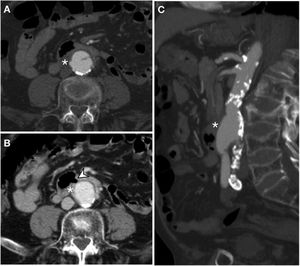

Primary aortoduodenal fistula in a 90-year-old male with haematemesis and severe abdominal pain in a context of acute aortic syndrome. Baseline computed tomography (CT) showed a large clot of 40 HU in the stomach (A) and a calcified aortic aneurysm (a) with loss of the fat plane achieving separation from the duodenal lumen (d) (B). CT with iodinated intravenous contrast (IVC) in the arterial phase (C) showed a penetrating ulcer (arrow) and active extravasation of IVC (arrow tip) towards the duodenum. MIP reconstructions on the coronal (D) and sagittal (E) planes showed the intimomedial flap (arrow) and the jet of IVC (arrow tip).

A 54-year-old male with Barrett's oesophagus who sought care due to signs and symptoms of upper gastrointestinal bleeding with haemodynamic instability. First, an endoscopy was performed which revealed a stenotic lesion in the proximal third of the oesophagus blocking the passage of the endoscope. When the patient experienced another episode of instability, it was decided to perform a computed tomography scan at baseline and following administration of iodinated intravenous contrast (IVC) with biphasic acquisition (only the arterial phase is shown). Axial slice (A) identifying an oesophageal parietal thickening (*) with serous infiltration obliterating the fat plane achieving separation from the aortic arch in relation to tumour spread. MIP reconstructions on axial (B) and sagittal (C-F) planes demonstrated active extravasation of IVC from the aortic arch towards the oesophageal lumen (arrow).